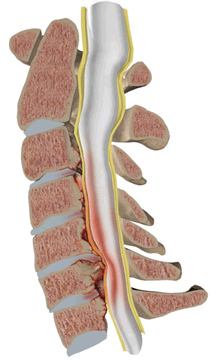

Стеноз позвоночного канала как самостоятельное заболевание чаще всего рассматривается на поясничном уровне позвоночника. Но встречается стеноз позвоночного канала и на шейном и грудном уровне позвоночника. Стеноз позвоночного канала связан с врожденными или приобретенными анатомическими изменениями в самих позвонках (костные остеофиты), а также в хрящевых и связочных образованиях, формирующих позвоночный канал.

Сужение поперечного сечения позвоночного канала может быть или следствием увеличения в размерах костных образований: дужек, суставных отростков, разрастания задних поверхностей тел позвонков, или в результате расплющивания позвонков и смещения их в просвет позвоночного канала.

Стеноз (сужение) просвета позвоночного канала со сдавлением спинного мозга с гипертрофией задней продольной и жёлтой связки.

Также к сужению позвоночного канала приводят гипертрофия желтой и задней продольной связок, увеличение толщины суставных капсул межпозвонковых суставов, смещения межпозвонковых дисков и фиброзного кольца, участвующих в формировании позвоночного канала.

Сужение позвоночного канала в переднезаднем направлении может быть обусловлено его вторичным стенозом, гипертрофией задней продольной и жёлтой связки, спондилолистезом. Для установления стеноза позвоночного канала необходимо измерение канала в сагиттальной плоскости. Абсолютным стенозом принято считать уменьшение диаметра канала до 10 мм и менее. Величина в 10-15 мм соответствует частичному стенозу. Толщина задней продольной связки в норме не должна превышать 2 мм, желтой связки — 3 мм.